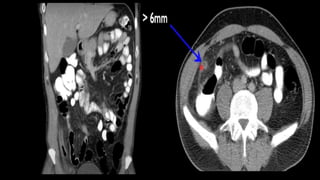

This document discusses the evaluation of right lower abdominal pain and lists appendicitis as a key cause. It notes that other potential causes include hemorrhagic cysts, heterotrophic pregnancy, salpingitis with pyosalpinx, funiculitis, and torsion of an undescended testis. The document was presented by Dr. A.S.M. Sufian of Cumilla Medical College Hospital and thanks the audience for their patience and listening.